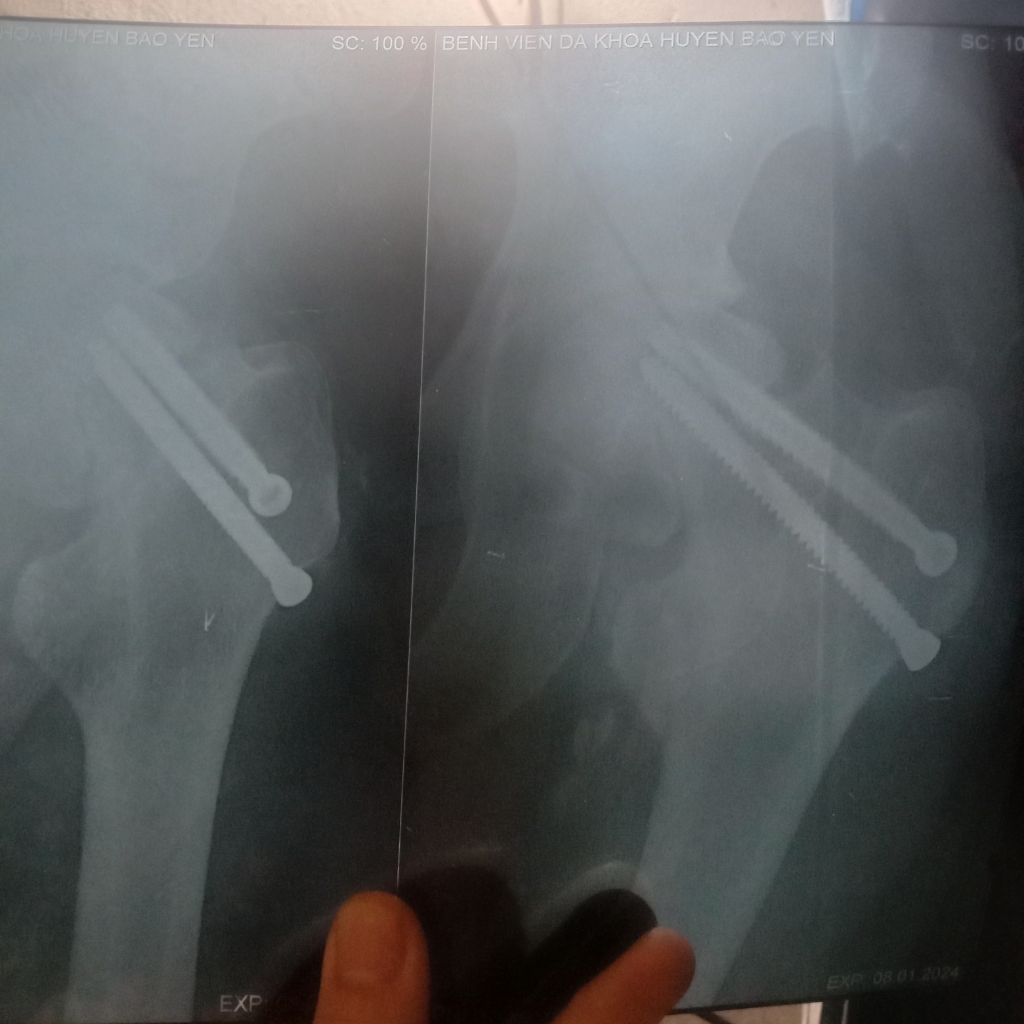

Đây là hình ảnh vít đinh của em ạ. Em thấy nó lệch lệch hay sao ạ bác sĩ.

Dương Thị Hạnh

Đinh này bs chẩn đoán hình ảnh sẽ giải thích em rõ hơn